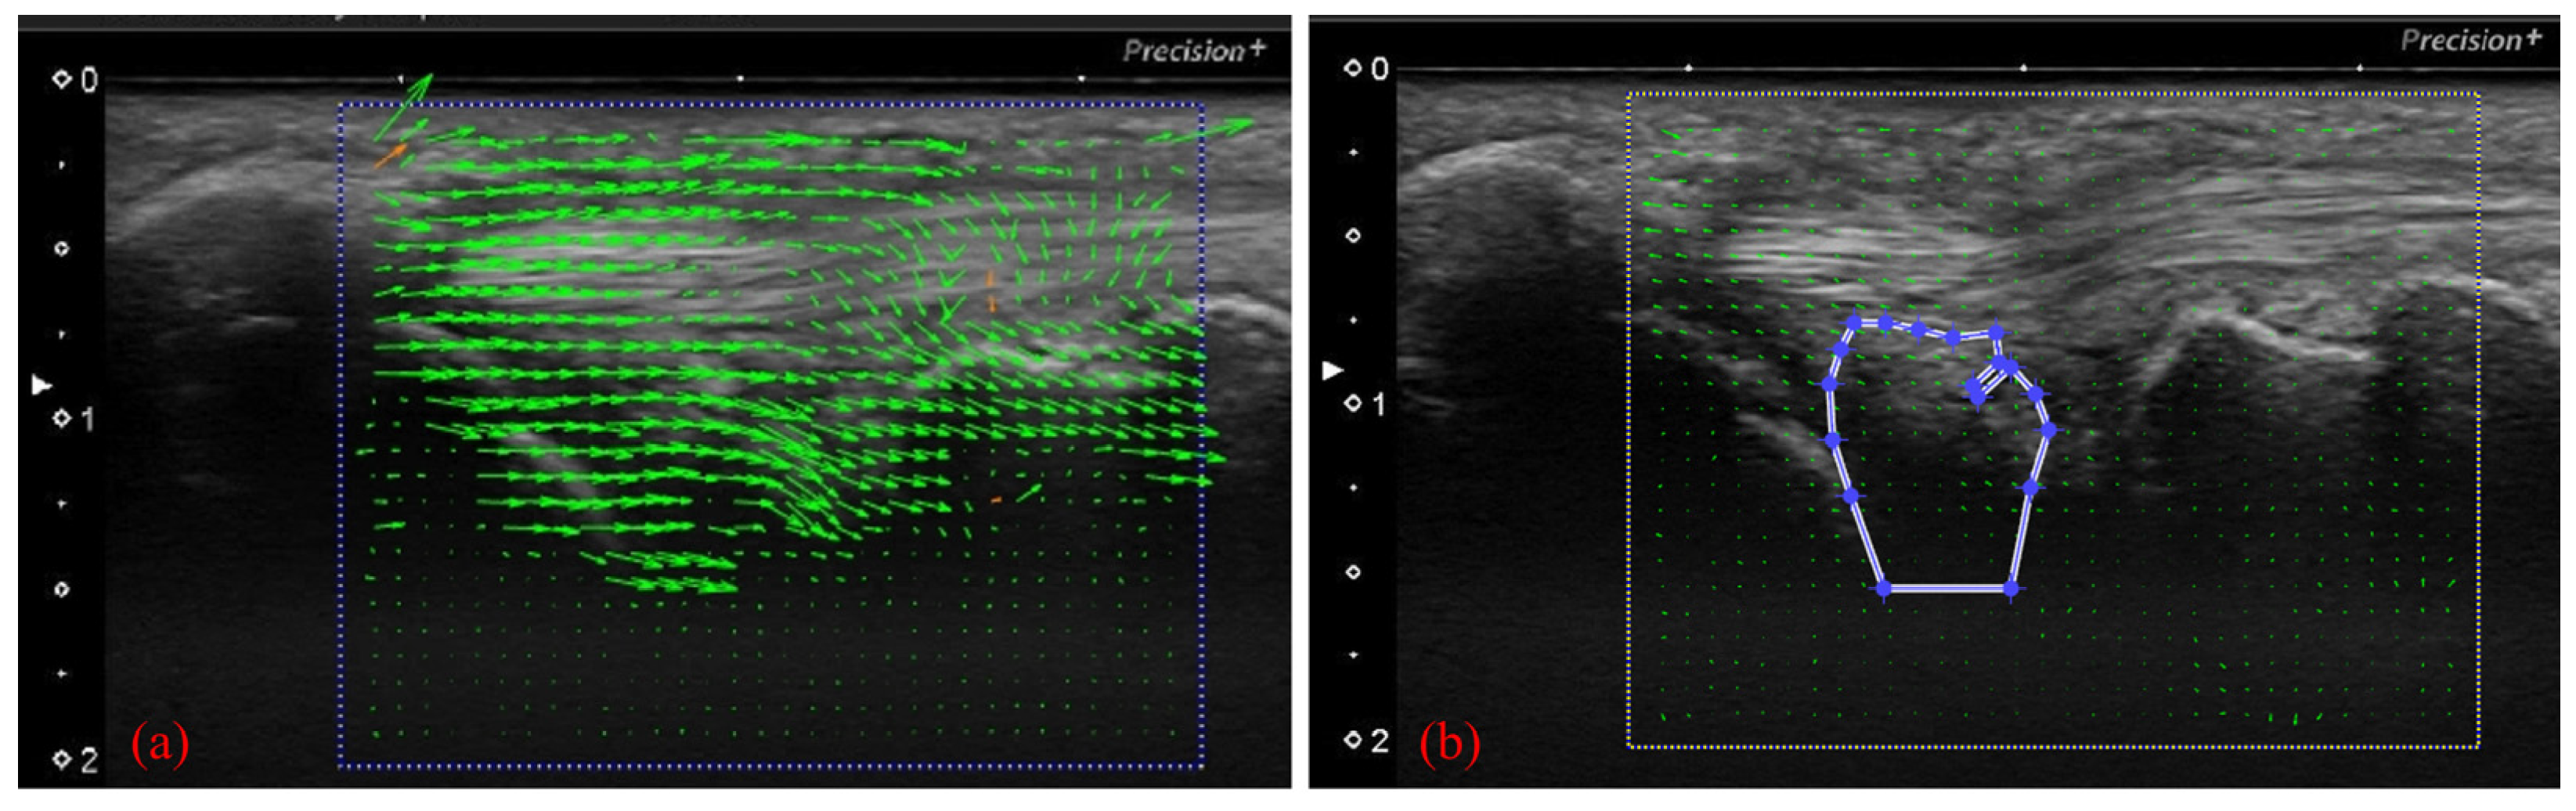

To perform motion analysis, TFCC visualization was performed with the forearm in pronation. Under these views, the wrist was actively moved from 15 degrees of radial deviation to 25 degrees of ulnar deviation at a 60-rounds-per-minute rhythm that was paced by a metronome (Figure 3). The same examination was performed twice per wrist. All US images were evaluated by two examiners (both senior orthopedic surgeons). As described previously, the articular disc was detected as a hypoechoic area [5]. Its area of measurement was defined by four lines as follows: proximal end of the articular disc, distal end of the articular disc, ulnar collateral ligament, and joint space between the lunate and triquetrum (Figure 4a). The area was calculated by using ImageJ software (USA National Institutes of Health [NIH], Bethesda, MA, USA), which is a public-domain Java-based image-processing software developed at the United States NIH [12]. Briefly, the areas of the defined articular disc were manually plotted and measured by using the Image J measurement tool (Figure 4b). Then, a comparison of the area of the articular disc between radial and ulnar deviation was performed. Furthermore, a correlation between patient height and the mean area of their articular disc was calculated. Measurements were performed by three orthopedic surgeons, using Image J. To confirm reproducibility, we calculated the intra-rater correlation coefficient and the inter-rater correlation coefficient by using these measurement results. Using the same images, the velocity magnitude of the articular disc displacement or ECU motion was analyzed by using PIV fluid measurement software (PIV lab. Version 2.36, add-in software from MATLAB (Mathworks, Natick, MA, USA)) [9]. Briefly, two regions of interest were set at the articular disc and ECU tendon (Figure 5). We edited all US movies into 30 static images per second. The pixel displacement between two sequential images was measured, and the velocity magnitude of the structure inside the region of interest was subsequently calculated. For the articular disc, the u-component, which comprises the longitudinal movement of the articular disc, was calculated. The v-component, representing the overall axial movement of the articular disc, was also calculated. Since the u- and v-components show positive and negative values depending on the direction of movement, the evaluation was added to the absolute values. PIV measurements were performed twice, with three examiners performing the measurements. The inter-rater and intra-rater correlation coefficients were evaluated.

Figure 5.

(a) Analyzing velocity magnitude image by using particle image velocimetry (PIV) fluid measurement software. With the US images, setting the articular disc and ECU tendon as regions of interest of the PIV. (b) Specification of the area to be measured (articular disc).